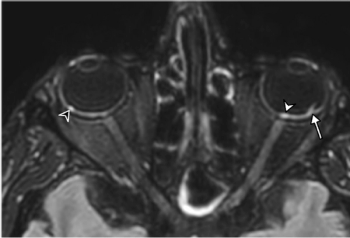

First brain MRI findings reveal dangerous COVID-19-related optical findings.

Research MRI images reveal information in 61-year-old COVID-19-positive patient that is similar to that captured by CT.